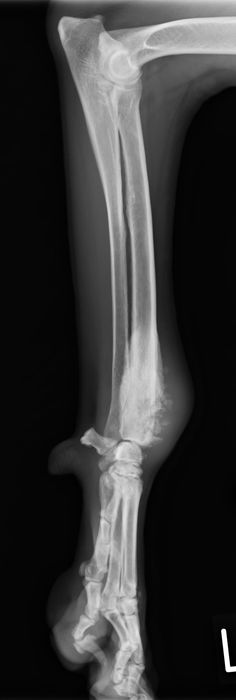

骨折治療について

動物も人間と同じように骨折や脱臼をします。

原因として交通事故などの大きな外力によるものもありますが、日本では小型犬が主体となっているため、ソファや抱っこしている所からの落下といった比較的小さな外力でも生じることが多くなっています。

骨折や脱臼の治療は、ギプスなどの処置のみで済むケースもありますが、ほとんどのケースは完全骨折や脱臼を生じますので、手術が必要となります。

当院における骨折治療は、動物のステータス、骨折の発生部位や分類などを考慮して「髄内ピン」「骨プレート」「創外固定器」を単独もしくは組み合わせて使用することで適当な固定力を得られるように施術しています。

●髄内ピン

0.8mm-5.0mmのステンレス製のピンを骨髄内に刺入して固定を行います。

●骨プレート

ステンレス製もしくはチタン製の金属の板(プレート)と骨ネジ(スクリュー)を使用して固定を行います。

●創外固定器

ネジ山があるピンを骨に刺入し、皮膚の外で連結バーとクランプを使用して固定を行います。

●髄内ピンと骨プレートの併用(プレート-ロッド併用法)

●髄内ピンと創外固定器の併用法(リニア型創外固定TypeⅠa "tie in")